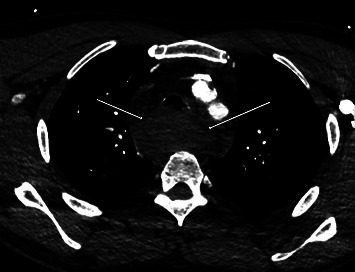

本病例讨论的是一名 47 岁的高加索男性,既往病史包括血脂异常、胃食管反流病、既往颈椎手术和焦虑症,在进行 C5-6 颈椎融合术后出现颈部血肿。医生紧急进行了颈部探查并清除了血肿,恢复了通气。患者被转入重症监护室,术后第 5 天拔管,伤口稳定,无残留出血。三周后复诊时,患者情况良好,胸片显示无渗出或血肿。本报告阐明了颈椎手术后颈部血肿并发症的急性临床症状及其与潜在病因的相关性、后续处理和结果所带来的挑战。

This case study discusses a 47-year-old Caucasian male with a past medical history of dyslipidemia, gastroesophageal reflux disease, previous cervical spine surgery, and anxiety who developed a neck hematoma postrevision of a C5-6 cervical spine fusion. Emergent neck exploration and evacuation of the hematoma were performed, and ventilation was restored. The patient was transferred to the intensive care unit and extubated on postoperative day 5 with a stable wound and no residual bleeding. At the 3-week follow-up appointment, the patient was noted to be doing well, with a chest radiograph showing no effusion or hematoma. This report elucidates the challenges posed by acute clinical symptoms and their correlation with the underlying cause, as well as the subsequent management and outcomes of a neck hematoma complication following cervical spine surgery.